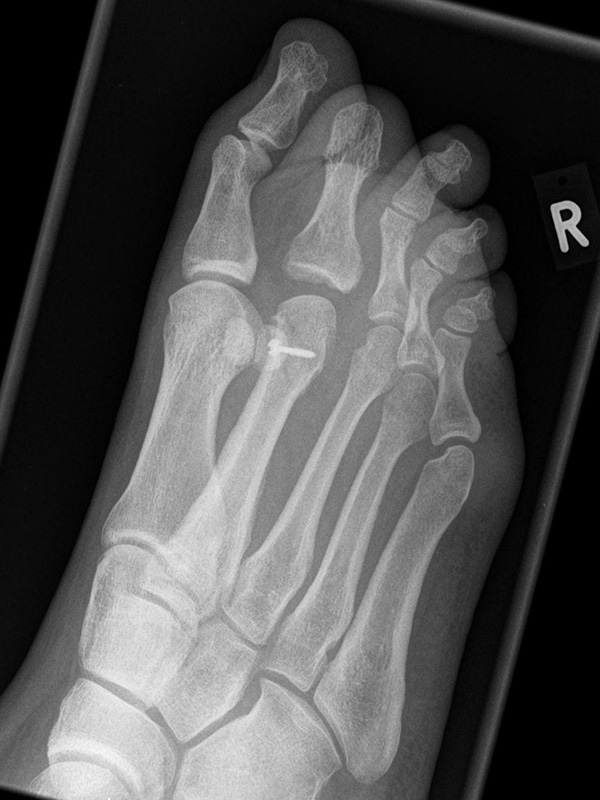

Vorfuß dorsoplantar (dp)

Positionierung:

• Patient liegt auf dem Rücken, der Fuß wird auf die Röntgenkassette aufgestellt, das Knie gebeugt.

• Der Zentralstrahl wird auf das Tarsometatarsalgelenk II zentriert.

• Die Röntgenröhre ist 15° vertikal gekippt.

• Anmerkung: Auch wenn der Fuß nicht belastet wird, sollte er auf die Röntgenkassette aufgestellt werden. Aufnahmen des hängenden Fußes sind nur eingeschränkt beurteilbar.

Kennzeichen des Röntgenbildes:

• Dorsoplantare Abbildung des Vorfußes.

• Tarometatarsale Gelenkreihe einsehbar.

• Winkelmaße können auf der unbelasteten Aufnahme des Vorfußes nicht beurteilt werden.

Besondere Bemerkungen zum Beispielbild:

• Verlaufskontrolle nach korrigierendem Vorfußeingriff bei Riesenwuchs des 2. Strahls mit verdicktem Os metatarsale II.

• Z.n. Amputation des Zehenendglieds D2.

• Z.n. Weil Osteotomie des Os metatarsale II.

• Hallux valgus interphalangeus.

Zur Vollansicht und zum Lesen der Bildbeschreibung bitte die Bilder anklicken.